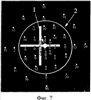

На фиг.7 изображено глазное дно пациентки Б. со светочувствительностью сетчатки после функционально неэффективной операции витрэктомии.

Пример 2. Поясняется фиг.5-8. Пациентка Б., 67 лет. Диагноз: идиопатический макулярный разрыв III стадии. Корригированная острота зрения 0,16. При анализе данных микропериметрии в центре разрыва выявляется наличие абсолютной скотомы, светочувствительность 0 децибел, по краю фовеа светочувствительность в среднем 10 децибел, точка фиксации расположена на крае разрыва на расстоянии 230 мкм от фовеа. Проведена субтотальная витрэктомия. Через 1 месяц после операции субъективно отмечается ухудшение качества зрения, корригированная острота зрения 0,1. Закрытие разрыва подтверждается оптической когерентной томографией. При проведении микропериметрии выявляется сохранение абсолютной скотомы и светочувствительности 0 децибел в центре фовеа, по краю фовеа светочувствительность 6 децибел, отсутствие смещения точки фиксации к центру фовеа. Эти данные позволяют сделать вывод о том, что хирургическое лечение является функционально неэффективным.